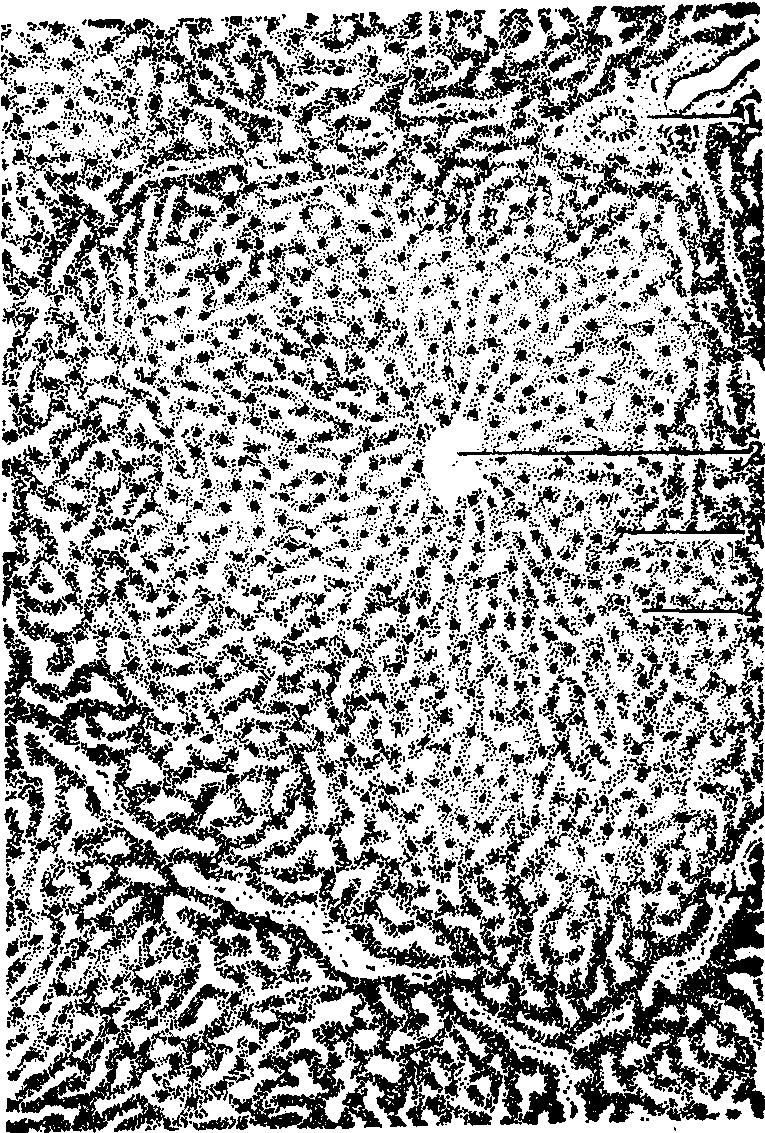

哺乳动物肝的构造 肝表面大部分被覆浆膜,湿润而光滑,其深面为致密结缔组织构成的被膜,在肝门处结缔组织增多并随血管和肝管分支入肝,构成肝的支架。根据肝的结构和功能特点,曾提出经典肝小叶(六边形)、门管小叶(三角形)、和肝腺泡(椭圆形)三种肝单位的概念(图1)。

图 1 三种肝单位示意图

经典肝小叶 即一般所称的肝小叶,为多面形的棱柱体,横切面呈多角形,周围有少量结缔组织分隔,血管、淋巴管和胆管分支穿行其中。小叶中央贯穿中央静脉,肝细胞单行排列成肝板分布于中央静脉四周。肝细胞较大,呈多角形,有1~2个大而圆的核,胞质内有丰富的细胞器和包含物。肝板有分支,互相吻合成网,板上还有彼此沟通的孔道,网孔内有窦状毛细血管,称肝血窦(图2)。窦壁有两种细胞,主要是有窗孔的内皮细胞。细胞间有较大间隙,多数哺乳动物内皮细胞外无基膜,只附有少量散在的网状纤维,故通透性较大,有利于血液与肝细胞间进行物质交换; 另一种是巨噬细胞或称枯否氏细胞。体积较大,形状多样,有多个突起,故又称星状细胞。其胞体突入腔内或游离于腔中,以突起附着于内皮细胞上。巨噬细胞对血液中的异物和胃肠来的细菌等有很强的吞噬能力,故有杀菌防病作用。肝细胞与内皮细胞之间有狭小间隙,称窦周间隙或狄斯氏间隙,是肝细胞与血液间进行物质交换的场所。间隙内充满了从肝血窦渗透出来的血浆,一般无红细胞,还有少量散在的网状纤维和贮脂细胞。后者为形状不规则的细胞,具有贮存脂肪和维生素A以及生成结缔组织纤维和基质等作用。肝细胞向窦周间隙的一面伸出许多微绒毛,有扩大肝细胞表面积的作用。

图 2 肝小叶构造

1. 小叶间动脉;2. 小叶间静脉;3. 血窦; 4. 肝板;5. 中央静脉; 6. 肝动脉分支; 7. 门静脉分支; 8. 肝管分支;9. 小叶间胆管; 10. 胆小管; 11. 小叶下静脉

在相邻肝小叶之间的小叶间结缔组织中,可见相伴行的四种管道,即小叶间动脉、小叶间静脉、小叶间淋巴管和小叶间胆管,合称门管,该区域称门管区。小叶间门管是肝门门管进入肝内的分支,包括肝动脉、肝门静脉、肝淋巴管和肝管等。猪、骆驼和熊的小叶间结缔组织较多,肝小叶分界明显; 其他哺乳动物的小叶间结缔组织少,肝小叶分界不清,可以门管的存在作为肝小叶的大致轮廓。